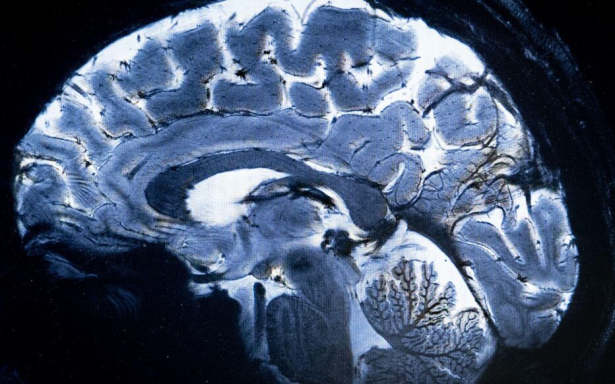

Médical

Voir n’est plus regarder : c’est comprendre la structure du monde cellulaire.

Loin du contraste classique, ϕ explore la richesse interne des tissus.

Elle distingue l’homogène du structuré, le bruit du sens, et redonne au regard médical une dimension topologique : celle de l’information vivante.

Les structures fines, souvent invisibles à l’œil nu, s’y dessinent comme des reliefs entropiques — un paysage du corps, révélé par la mathématique du vivant.